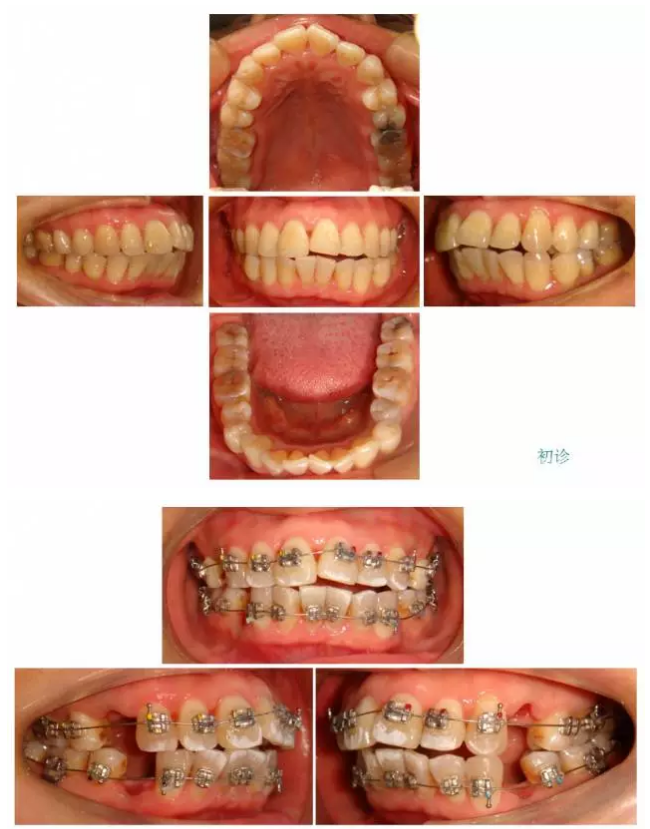

【原創(chuàng)博客】這樣的代償矯治大家滿意嗎?(重度骨性二類)——侯志明

QQ圖片20150824150825.png

QQ圖片20150824150547.png

QQ圖片20150824150559.png

QQ圖片20150824150613.png

QQ圖片20150824150628.png

QQ圖片20150824150643.png

QQ圖片20150824150701.png

QQ圖片20150824150716.png

QQ圖片20150824150729.png

QQ圖片20150824150743.png

QQ圖片20150824150805.png